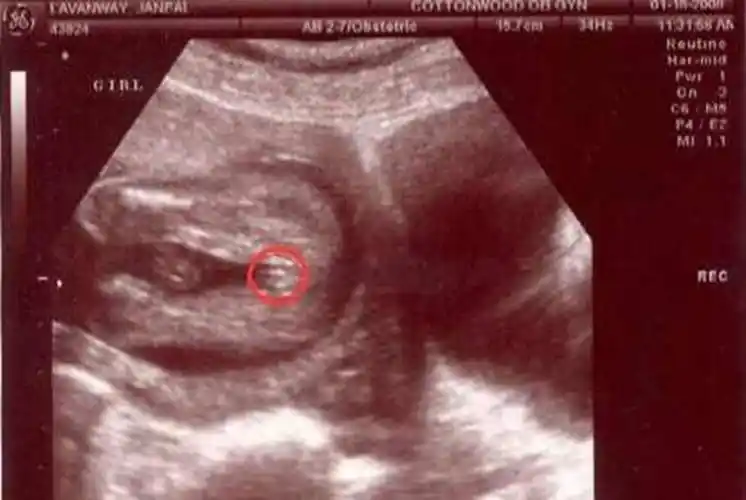

胎儿的生殖器来判断,而且一般是需要在怀孕4个月左右通过b超才可以

一般在怀孕9到12周的时候就是怀孕三个月,在怀孕三个月的时候,胎儿在